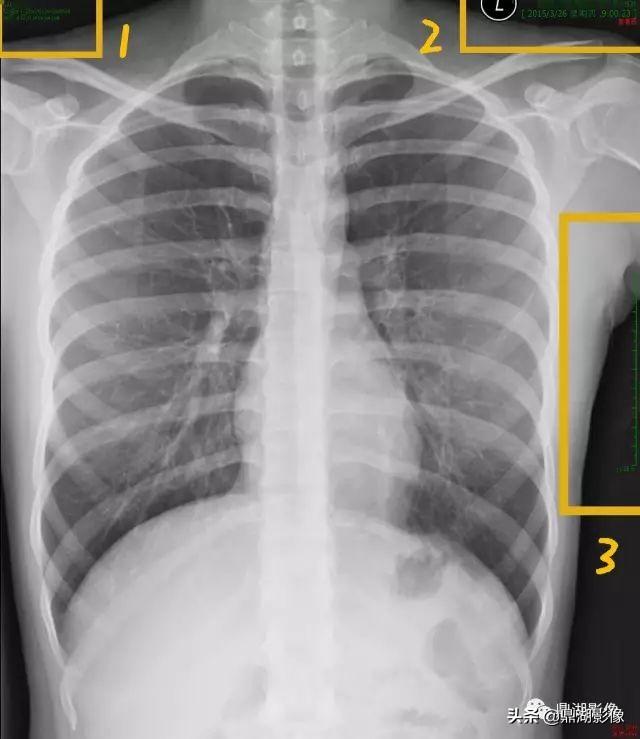

X线片

这是一张胸部正位片,图像一般分为几个区,右上为患者及检查信息,左上为机器及图片信息,右下为显示视野。

图中圆框内标记的A、P、R、L为方位,分别为前后右左;黄色标记3区指向为刻度尺比例,1分隔为1CM,可自行对比量病变大小。

图中1区放大可见

1. 最上方为患者姓名,一般为汉语拼音,有的是汉字标示;

2. 患者年龄、性别及影像检查号,其中M为男性,F为女性;

3. 影像登记流水号,告诉患者登记的顺序,如图中说明这个患者是2015年3月26号第8个登记的;

4. P000***这个号码是病人编号,每个就诊者有且只有一个病人编号。

放大2区可见:

1. 所做检查医院名称,一般带有XX Hosptial或XX医院;

2. 检查日期,顺序为年月日;

3. 检查时间,精确到秒;